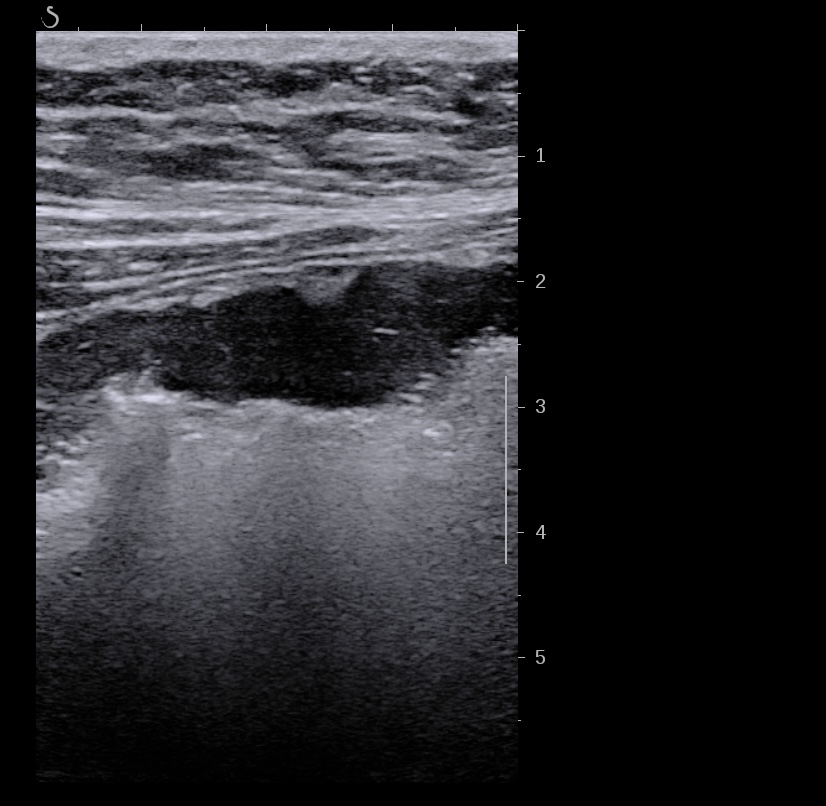

Echographie des cas numéro 2 puis 3

Epaississement entre 4.5 et 7 mm selon les segment, la structure en couche disparait totalement par endroit, à d’autre elle est partiellement conservée. Activité doppler intense de la paroi

Le Score de Milan (MUC) est à (1,4 x7+2) = 11,8

Là encore la paroi est très hypoéchogène, la structure en couches est par endroit totalement absente, ulcérations en surface, infiltration de la graisse, doppler intense, petites adénopathies périphériques.

Le rectum est bien vu avec la sonde basse fréquence la paroi atteint 10 mm à ce niveau.

Le score de Milan MUC est de (10 x1,4+2) = 16